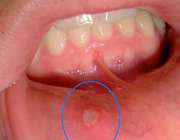

بیشتر مواقع زخم‌های دهانی خفیف اند و خود به خود بهبود می‌یابند. علت زخم‌های دهانی می‌تواند عفونت، ضربه و یا حساسیت دارویی باشد. علاوه بر آن می‌تواند به عنوان علامت یک بیماری نظیر سرطان در نظر گرفته شود.

«زخم‌های دهانی به دو دسته آفت و تب‌خال تقسیم می‌شوند که شدت وقوع آنها از ضعیف تا شدید است.

بیشتر مواقع این زخم‌ها خفیف اند و خود به خود بهبود می‌یابند. علت زخم‌های دهانی می‌تواند عفونت، ضربه و یا حساسیت دارویی باشد. علاوه بر آن می‌تواند به عنوان علامت یک بیماری نظیر سرطان در نظر گرفته شود.

ضعیف معمولا به قطر نیم سانتیمتر و با مرکز سفید یا زردرنگ هستند که با التهاب قرمز رنگ احاطه شده‌اند. حاشیه زبان، گونه‌ها و لب‌ها مناطقی هستند که زخم‌های دهانی معمولا در این مناطق ایجاد می‌شوند. بهبود این زخم‌ها معمولا بین 5 تا 14 روز طول می‌کشد.

وقوع آفت‌های شدید، معمول نیست و علاوه بر حاشیه زبان، گونه و لب‌ها، کام و انتهای گلو را نیز درگیر می‌کند. بهبود این آفت‌ها معمولا بین 10 تا 30 روز زمان می‌برد.